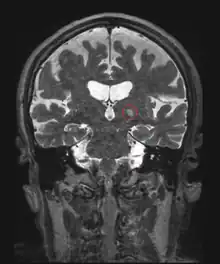

HIFU is combined with other imaging techniques such as medical ultrasound or MRI to enable guidance of the treatment and monitoring.

Neurological disorders

One of the first applications of HIFU was the treatment of Parkinson's disease in the 1940s. Although ineffective at the time, HIFU has the capacity to lesion pathology. A focused ultrasound system is approved in Israel, Canada, Italy, Korea and Russia to treat essential tremor,[6] neuropathic pain,[7] and Parkinsonian tremor.[8] This approach enables treatment of the brain without an incision or radiation. In 2016, the US Food and Drug Administration (FDA) approved Insightec's Exablate system to treat essential tremor.[9] Treatment for other thalamocortical dysrhythmias and psychiatric conditions are under investigation.[10]

Image guidance

HIFU therapy requires careful monitoring and so it is usually performed in conjunction with other imaging techniques.

Pre-operative imaging, for instance CT and MRI, are usually used to identify general parameters of the target anatomy. Real-time imaging, on the other hand, is necessary for safe and accurate noninvasive targeting and therapy monitoring. Both MRI and Medical ultrasound imaging have been used for guidance in FUS treatment. These techniques are known as Magnetic Resonance guided Focused Ultrasound Surgery (MRgFUS)[32][33] and Ultrasound guided Focused Ultrasound Surgery (USgFUS) respectively.[4][34] MRgFUS is a 3D imaging technique which features high soft tissue contrast and provides information about temperature, thus allowing to monitor ablation. However, low frame rate makes this technique perform poorly in real-time imaging and high costs represent a significant limitation to its use.[35] USgFUS, differently, is a 2D imaging technique in which, although no system to provide quantitative information on temperature has been commercially developed so far, several benefits are exploited, such as high frame rate (up to 1000 images per second), low cost and minimal adverse health effects. Another reason why ultrasound is ideal for image guidance is it verifies the acoustic window in real time since it is the same modality as the therapy.[36] The implication of this is that if the target region is not visualized by ultrasound imaging before and during HIFU therapy, then it is unlikely that HIFU therapy will be effective in that specific region.[36] In addition, treatment outcomes can be estimated in real time through visual inspection of hyperechoic changes in standard B-mode images.[37]